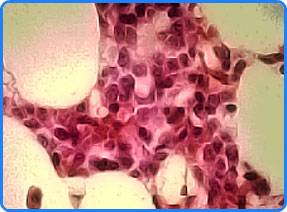

The image above shows Bone Marrow Hematopoetic cells after 25 minutes in solution of DeltaCAL